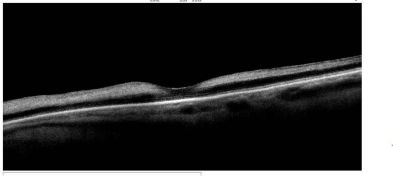

Dome-shaped maculopathy:[31]

It is an anterior convex protrusion of the macula toward the vitreous cavity seen on OCT. It is associated with high myopia and posterior staphyloma.

It exhibits a posterior globe bulge, resulting in a deep concave B-scan OCT and distorted retinal structures.